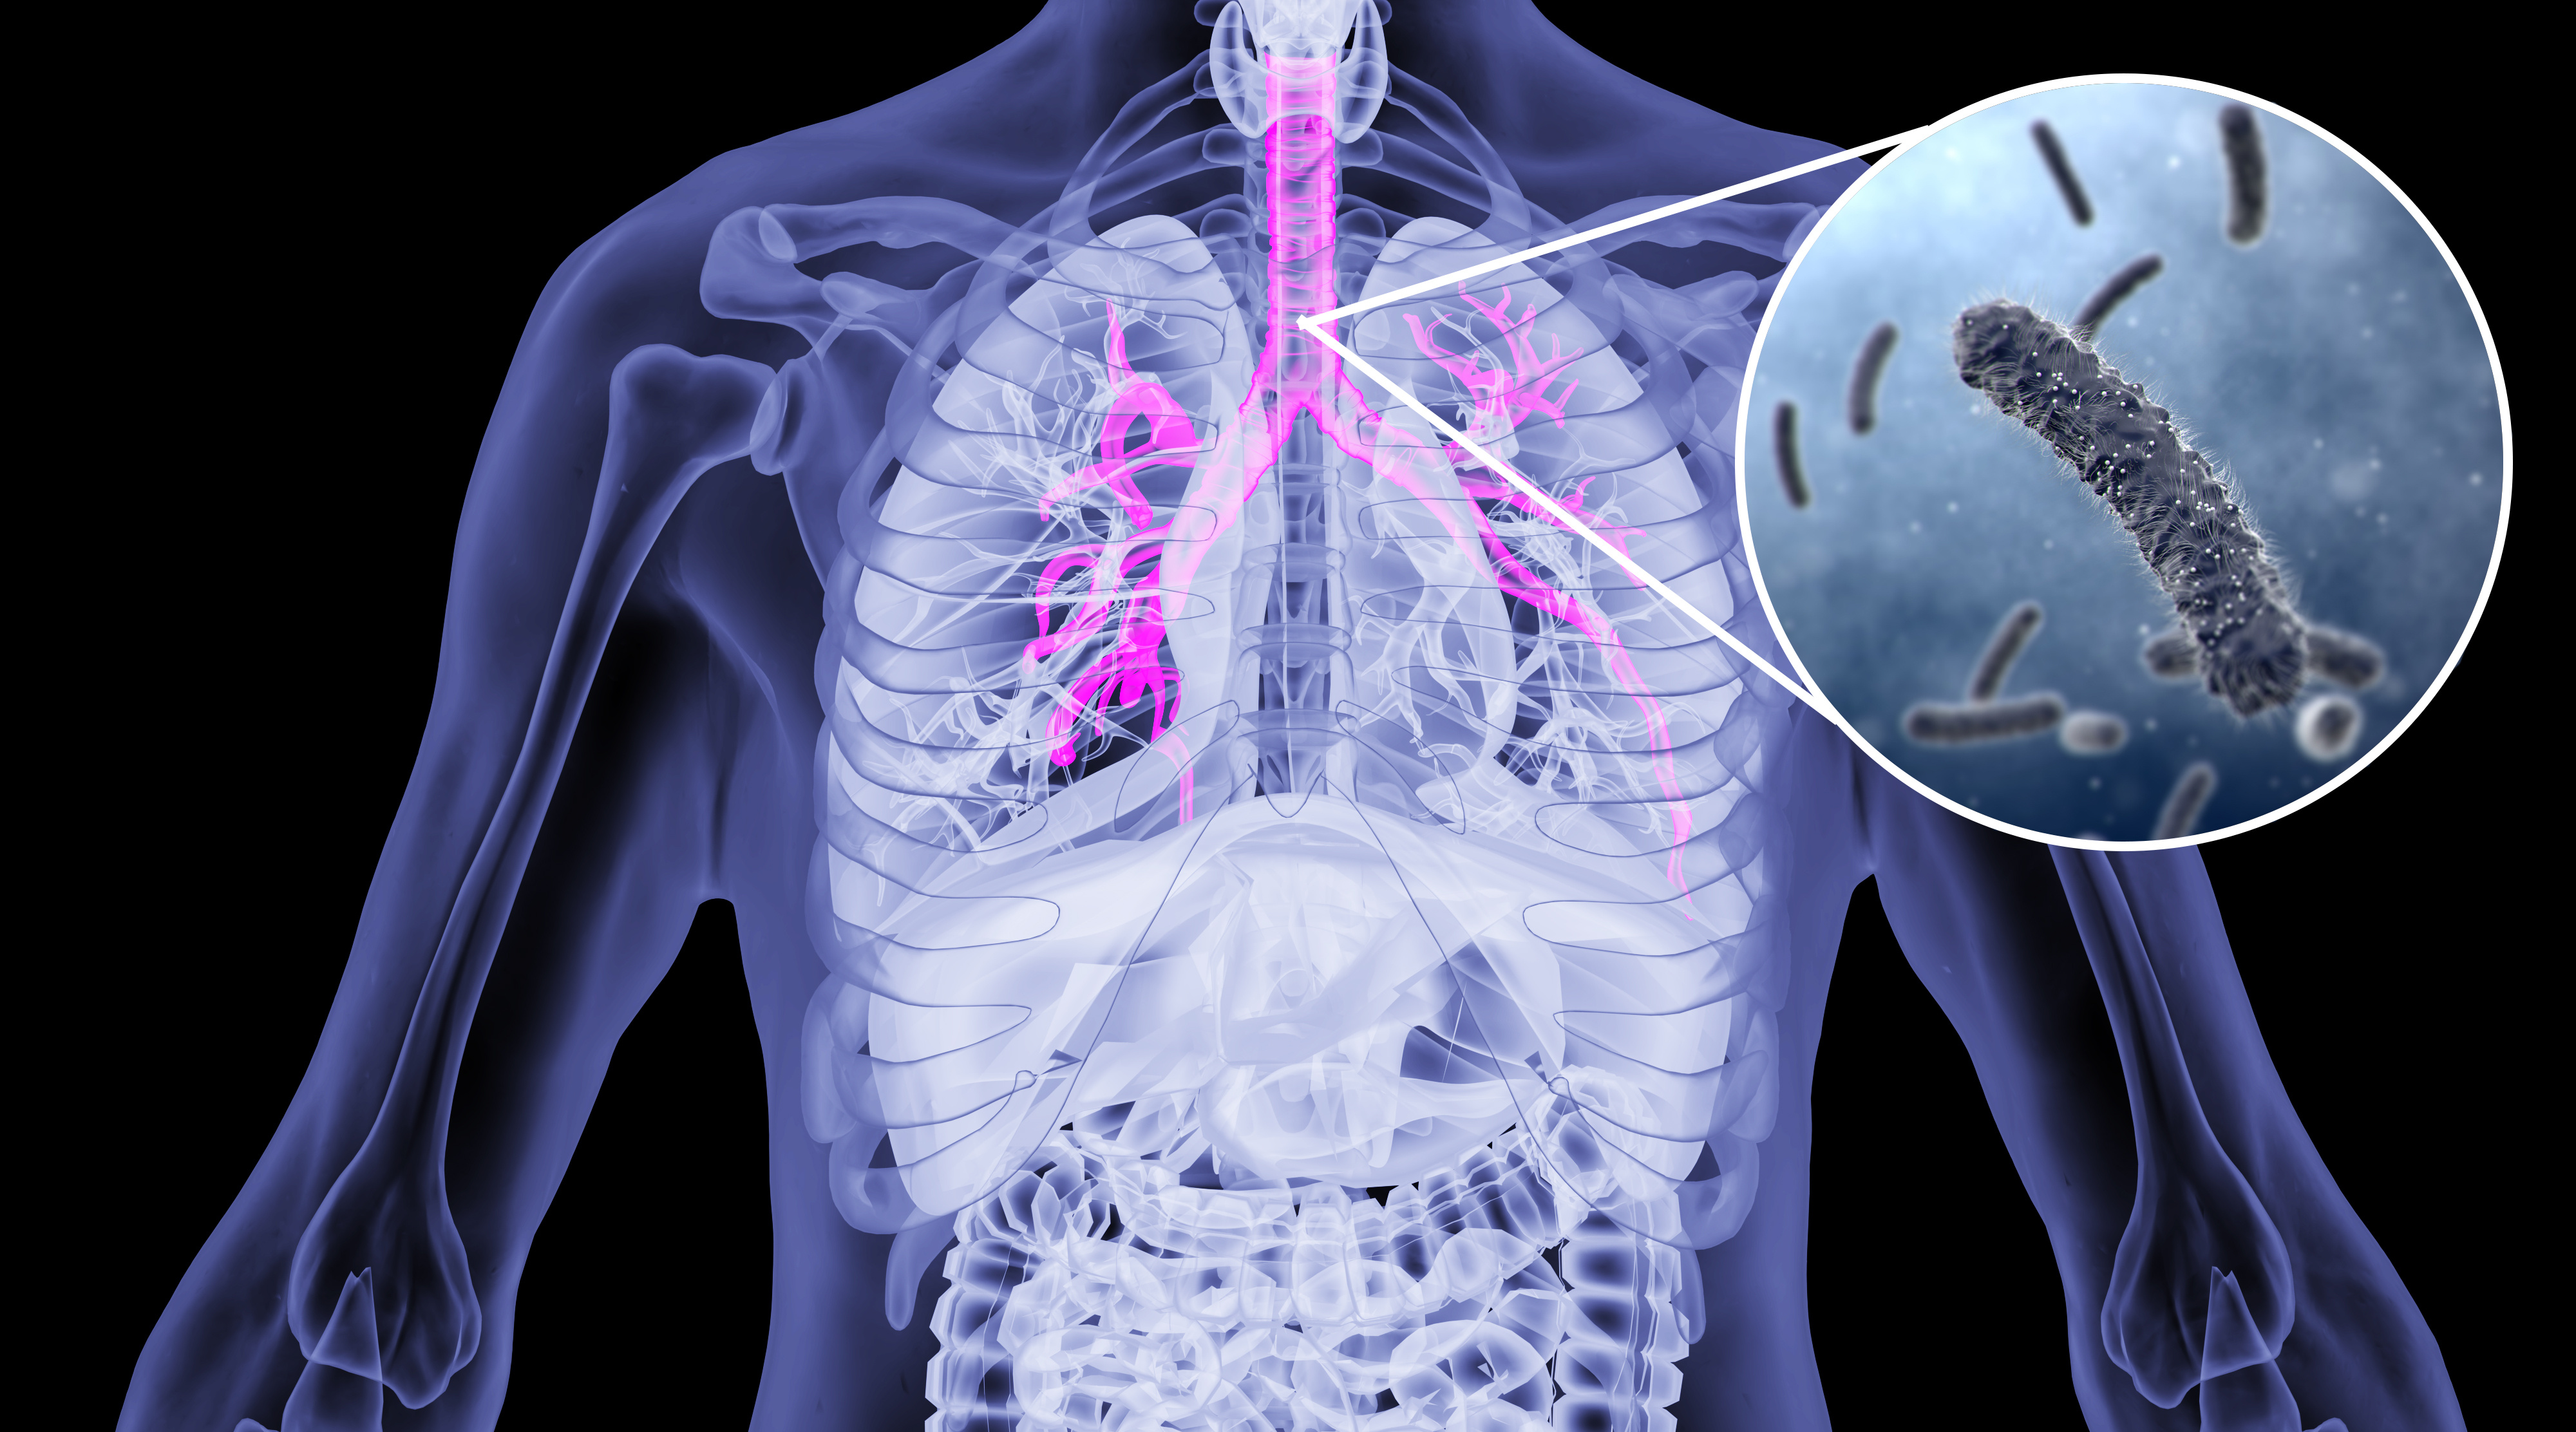

呼吸道感染疾病常见秋冬季,其中呼吸道感染70%以上由病毒引起[1]。呼吸道疾病成为我国5岁以下儿童的死亡主要原因之一。据统计,每年儿童发生病毒性呼吸道感染的中位数是5次,更有10%的儿童每年发生多达10次以上的呼吸道病毒感染[3-4]。全年皆可发病,秋冬季较多。

流行病学统计结果表明,甲型流感病毒、乙型流感病毒、呼吸道合胞病毒、腺病毒、副流感病毒是引起呼吸道感染最常见的病原体[1-2],另外人鼻病毒、肺炎支原体、百日咳杆菌也容易引起呼吸道疾病。

呼吸道感染后的临床表现复杂且相似,不同病原体引起的呼吸道疾病,临床用药也不同,因此精准检测病原体的种类显得尤为重要,病原体的核酸检测是鉴别病原种类有效方法之一。2020年版《流行性感冒诊疗方案》、2023年版《百日咳诊疗方案》和2023年版《儿童肺炎支原体肺炎诊疗指南》中均推荐了核酸检测病原体的方法。